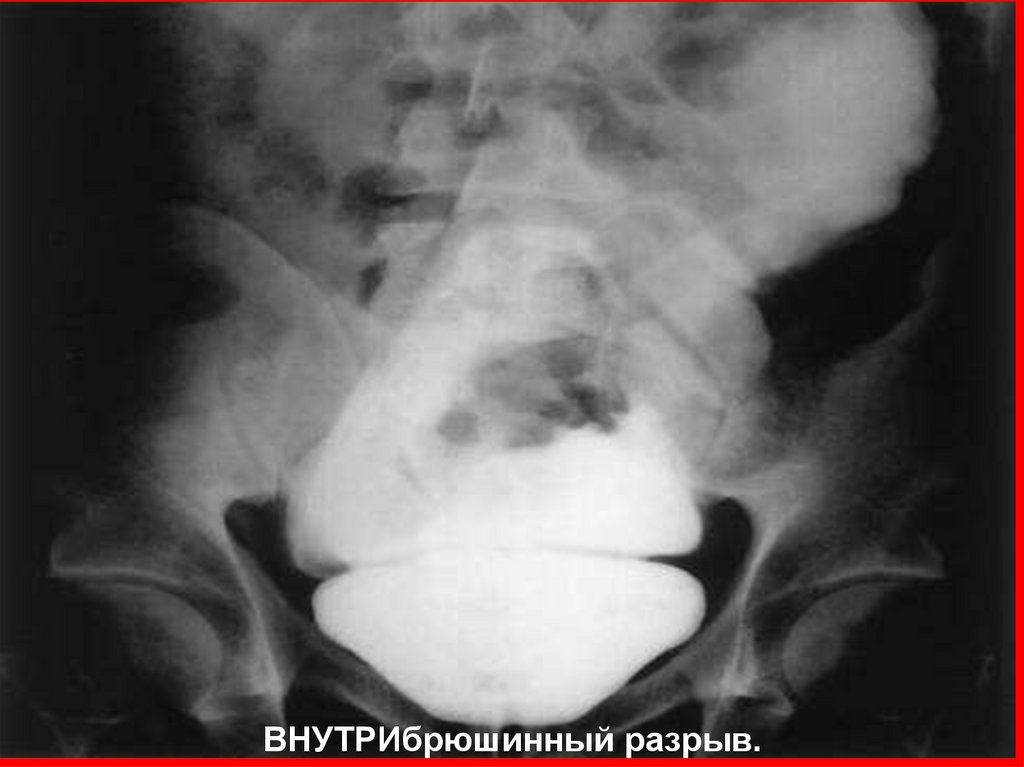

79.

ВНУТРИбрюшинный разрыв.